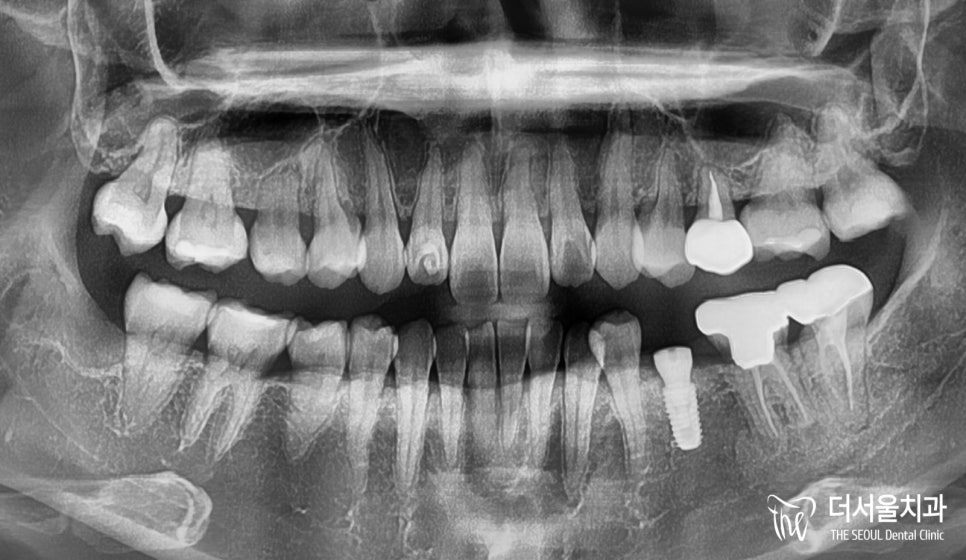

붉은색 동그라미로 표시된 곳을 보면

유치로 뿌리가 다른 것들에 비해

되게 짧다는 것을 확인할 수 있습니다.

튼튼히 고정될 수 없는 상태로

흔들림 체크를 했더니

조금 더 있으면 빠질 것 같았습니다.